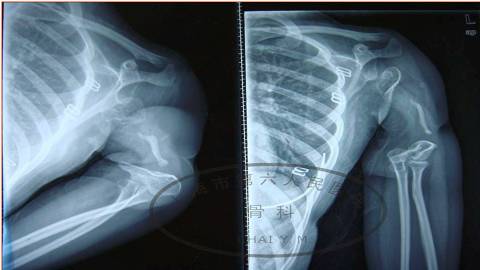

这是一个极端的情况,这是一个女性18岁。

她小时候8岁的时候,得了肱骨骨髓炎。现在十年过去了,发育的后果,大家可以看到,左上臂严重的短缩。

从X光片上可以看到,她的肱骨全长是缺损的,但是肩关节还有一部分肱骨头的存在。

我们在CT可以看到,这个头还是有一些基本结构,DSA也可以看到,她有足够吻合的血管。

在这种情况下,我们设计一个游离腓骨。

首先我们探查肩关节的时候,可以看到肩袖的部分,还有三角肌的部分,它还是有一定功能。

因此我们设计的腓骨,就直接采用长段的骨缺损的恢复。利用长段的腓骨,来代替全长的肱骨。

手术后三个月,骨折得到愈合。

从术前和术后的比较看,我们看左上肢得到了明显的延长。

更重要的是,这个小孩恢复了她上肢的支撑功能,所以三个月的时候,她可以上举,可以曲肘,可以梳头,可以吃饭这些动作,对她是比较有利的。